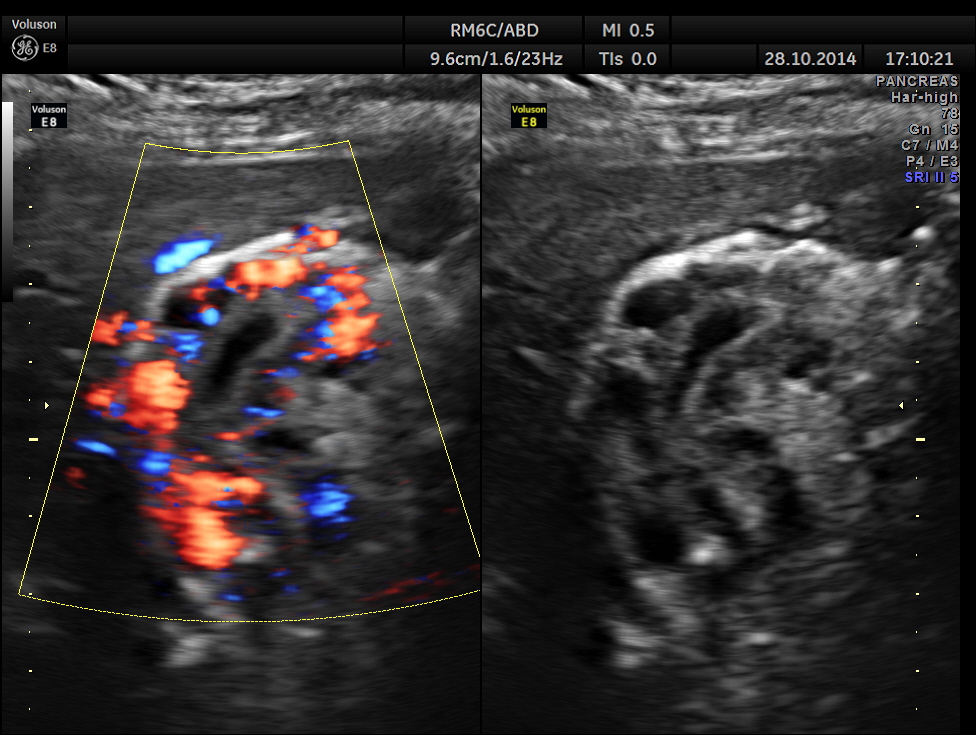

Colour flow imaging of the same

Main portal vein show flow reversal ( blue colour ) – centri-fugal flow suggestive of portal hypertension.

Mild splenomegaly with mildly dilated splenic vein is seen.

Epigastric varices are also seen.

This patient has cirrhosis of liver with portal hypertension – flow reversal of main portal vein , splenomegaly , mildly dilated splenic vein and varices around the gallbladder.